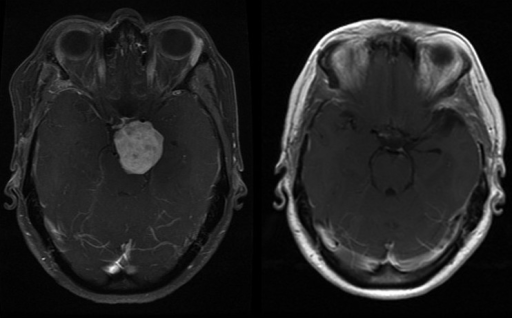

Contributor: Aaron Lessen, MD Educational Pearls: The cause of Alzheimer's disease is multifactorial, but the most widely suspected mechanism is the amyloid cascade hypothesis: Beta-amyloid proteins accumulate in the central nervous system, forming plaques that impair neuronal function. In recent years, advances have led to the development of targeted therapies with monoclonal antibodies. These drugs: Work by degrading amyloid plaques Slow the rate of cognitive decline and disease progression Have major side effects, most notably the development of amyloid-related imaging abnormalities (ARIA) ARIA may present as edema, effusion, or microhemorrhages, which are only detectable on MRI Symptoms can include headache, vertigo, or focal neurologic deficits that mimic stroke For patients presenting to the emergency department with stroke-like symptoms, it is important to consider whether they have a history of Alzheimer's disease and whether they are taking these medications. This guides decisions about imaging and treatment: The work-up may require MRI, which can delay thrombolytic or endovascular therapy in patients with true strokeConversely, treating a patient with ARIA using thrombolytics increases the risk of bleeding and other complications References Ebell MH, Barry HC, Baduni K, Grasso G. Clinically Important Benefits and Harms of Monoclonal Antibodies Targeting Amyloid for the Treatment of Alzheimer Disease: A Systematic Review and Meta-Analysis. Ann Fam Med. 2024 Jan-Feb;22(1):50-62. doi: 10.1370/afm.3050. PMID: 38253509; PMCID: PMC11233076. Ma C, Hong F, Yang S. Amyloidosis in Alzheimer's Disease: Pathogeny, Etiology, and Related Therapeutic Directions. Molecules. 2022 Feb 11;27(4):1210. doi: 10.3390/molecules27041210. PMID: 35209007; PMCID: PMC8876037. Perneczky R, Dom G, Chan A, Falkai P, Bassetti C. Anti-amyloid antibody treatments for Alzheimer's disease. Eur J Neurol. 2024 Feb;31(2):e16049. doi: 10.1111/ene.16049. Epub 2023 Sep 11. PMID: 37697714; PMCID: PMC11235913. Summarized by Ashley Lyons, OMS3 | Edited by Ashley Lyons and Jorge Chalit, OMS4 Donate: https://emergencymedicalminute.org/donate/